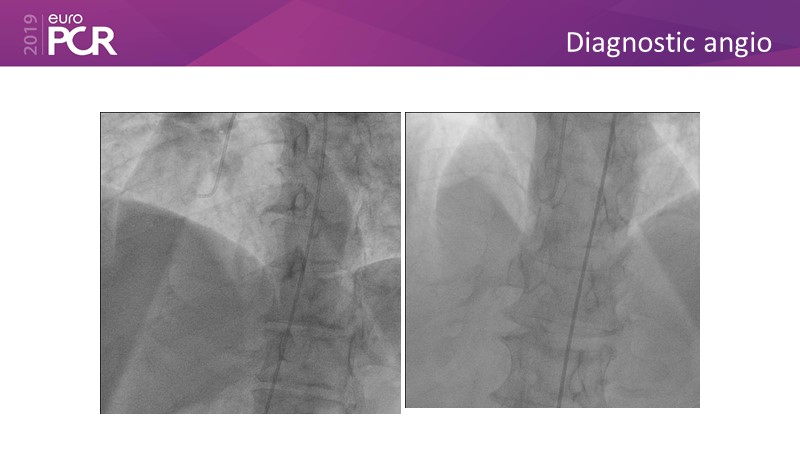

Distal left main stenosis: how to treat optimally with dedicated bifurcation stent BiOSS Lim C. Case-based session